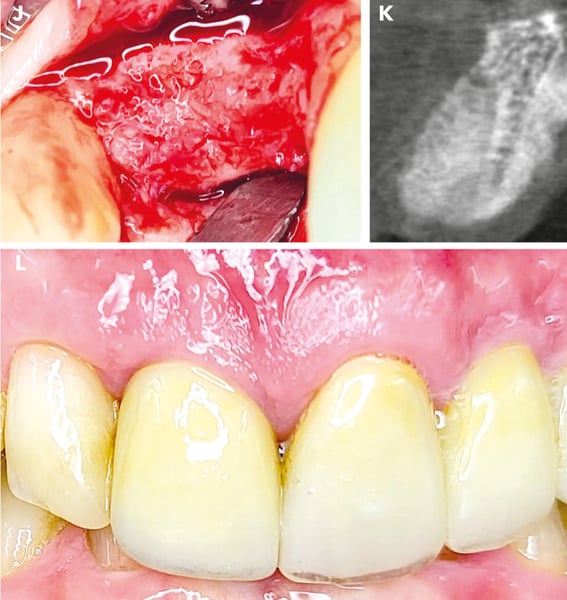

Alveolar ridge preservation. Tooth extraction (Figure F) revealed apical granulation. After mechanical cleaning, the socket was filled with allogenic bone substitute mixed with hyaluronic acid (Figure G). To optimize soft tissue healing, a PRF plug was placed in the socket and secured with a situational suture (Figure H). The postoperative control image (Figure I) shows the vestibular oversizing of the inserted material

Final situation. After 4 months, when the surgical site was reopened (Figure J), a completely regenerated alveolar ridge was revealed. The alveolus showed complete radiological regeneration (Figure K), allowing for straightforward implant placement. Figure L illustrates the final prosthetic restoration with irritation-free mucosa conditions after one year